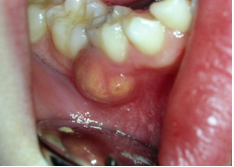

| Absceso por caries penetrante |

Un absceso dental es una acumulación de material purulento (pus) resultante de una infección de origen dental.

Este, produce destrucción del tejido óseo (hueso) que rodea a la raíz dental y puede producir una fístula.

La infección de origen dental puede ser ocasionada por una caries penetrante (penetra hasta la pulpa del diente infectándola), tratamiento de conductos fallidos o mal realizados, por un traumatismo (golpe) o restauraciones (resinas, amalgamas, etc) dentales muy amplias o profundas.